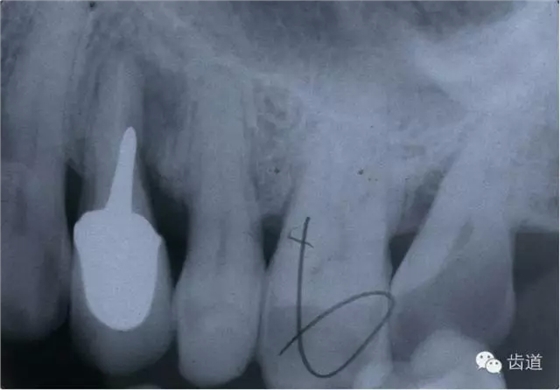

左上4鑄造樁側(cè)穿

(二)髓腔壁穿孔的診斷及處理

1.診斷:自覺疼痛。

2.檢查:探診疼痛,且有鮮血;用根管長(zhǎng)度測(cè)量?jī)x探測(cè)可疑穿孔處,儀器發(fā)出報(bào)警聲;插診斷絲到可疑穿孔處拍X線片,可見診斷絲已超出髓腔范圍。